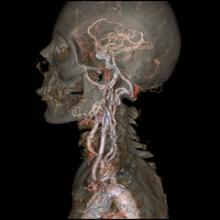

Physicians have used radiation in medicine for more than a century. The use of radiation in diagnostic imaging, including computed tomography (CT), fluoroscopy, angiography, mammography, computed radiography (CR) and digital radiography (DR), as well as in nuclear medicine, has aided greatly in the diagnosis and treatment of cancer and other diseases.